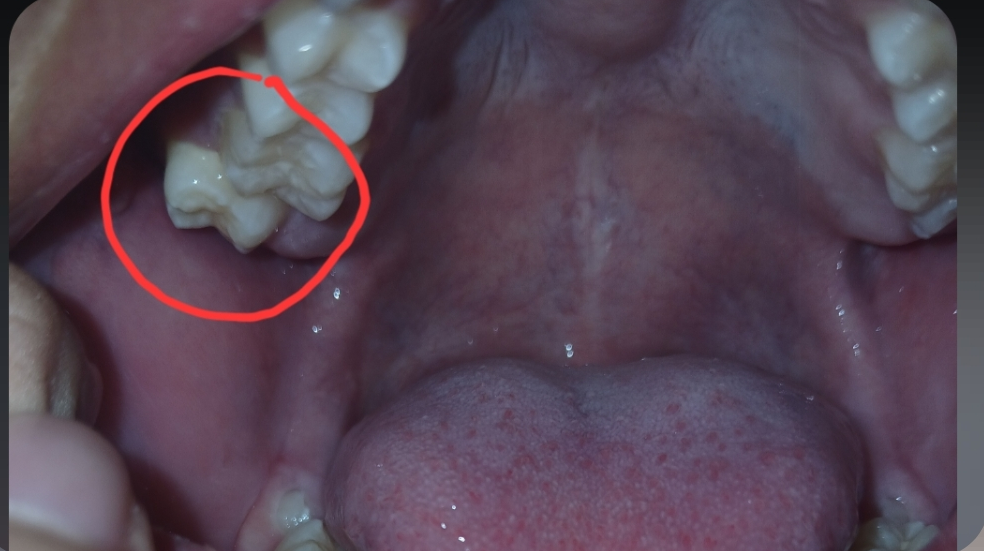

ใช่ฟันคุดมั้ยครับ

คือผมรู้สึกปวดตรงเหงือกที่ฟันเอียงนี้เวลาทำท่าแก้มป่องเลยสงสายว่าเหงือกอาจจะเป็นแผลรึป่าว แต่พอลองส่องดูดันเห็นว่าฟันมันเอียงขนาดนี้ ปกติไม่ได้เอียง พึ่งเป็นมา2-3วันนี้ครับ เบื้องต้นผมต้องทำยังไงบ้างครับ เครียดมาก ต้องผ่ามั้ย🫠🫠